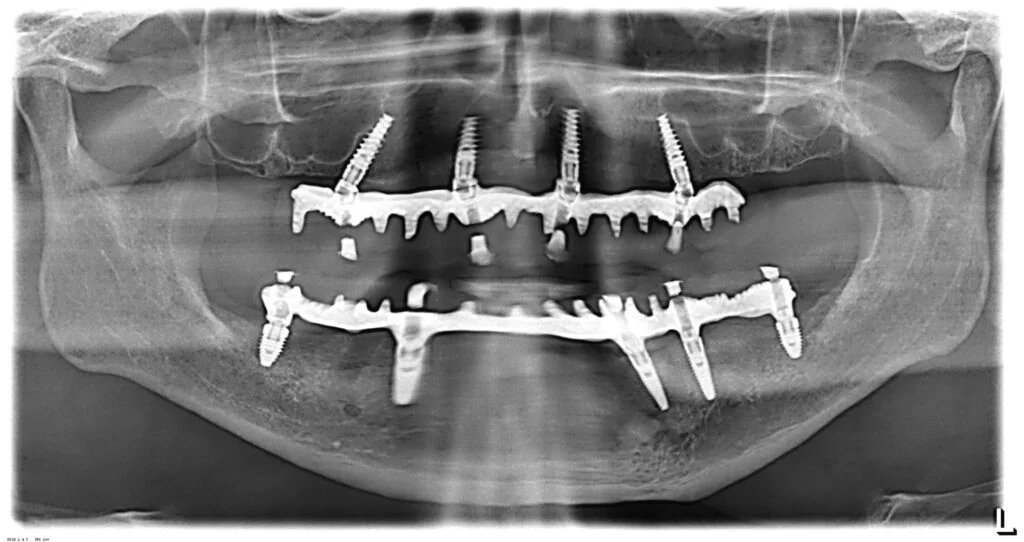

All on Four Implants

What is All on Four?

All On Four is a new concept in implantology, where we can replace all the teeth with fixed prosthesis with the help of FOUR implants in each jaw.

Why it works

This is particularly used in patients with severe bone loss where conventional implants cannot be placed. It avoids lengthy Sinus Lift surgeries.

Elite Implantology

Zygomatic Implants

A Specialist Job.

MDS Surgical Mastery

Zygomatic implants are an advanced implant technique where they are fixed to the Zygomatic arch for the upper jaw.

Eliminating the use of bone grafts, these implants allow you to get the prosthesis within 24 to 72 hours, unlike conventional implants that require months of waiting.